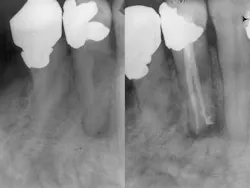

Thermoplastic obturation takes several different forms. Carrier-based thermoplastic systems have evolved away from metal and plastic carriers to the point where they are now constructed of two different phases of gutta-percha, with the outer layer thermoplasticized far more than the inner core, which acts as the carrier. All thermoplastic techniques require the minimum placement of cement, because the coronal pathway for the release of excess cement is occluded first, eliminating the escape valve when room temperature systems are employed. Another thermoplastic approach is the use of a heated spreader that first requires the placement of a conventional gutta-percha point to the constriction followed by heated vertical condensation within 5 mm of the apex and conventional condensation within 2 mm of the apex. This form of thermoplastic obturation adapts the gutta-percha to the walls of the canal within the last 2-3 mm of the canal. Interestingly, the gutta-percha that was placed at room temperature is not affected by the heat introduced by the spreader and remains more or less in the same position as when it was originally placed. Strictly speaking, the most apical placement of the gutta-percha has not been thermoplasticized and is essentially a single-point fill. The advantage is no shrinkage.

ADDITIONAL READING |Trauma and horizontal root fractures of the anterior teeth: A review and case report

After adaptation of the point to the canal wall via the heated spreader, a void extending from the most apical 2 mm of gutta-percha to the orifice is present. This space is then filled using one of several available glue guns that deposit thermoplasticized gutta-percha through a thin, silver needle. Being thermoplasticized, the entire deposited body of gutta-percha will shrink as it cools to body temperature again, compromising the concept of a true three-dimensional fill. The same problem occurs when the squirt technique is applied, a form of obturation that skips a heated spreader and goes directly to the extrusion of molten gutta-percha from the constriction to the orifice. Again, shrinkage is unavoidable.